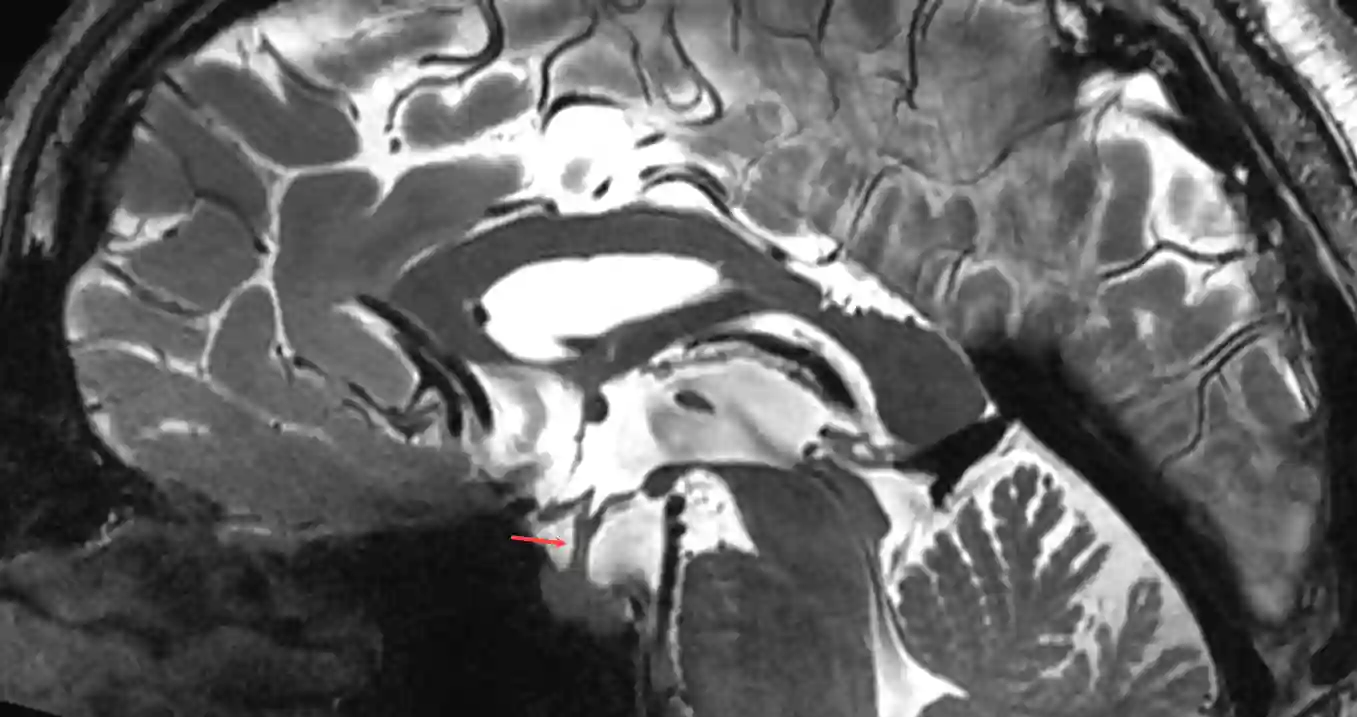

Hypophysenstiel im MRI

Darstellung des Hypophysenstiels (roter Pfeil) in einer sagittalen T2 Sequenz eines 7 Tesla MRI Bilds.